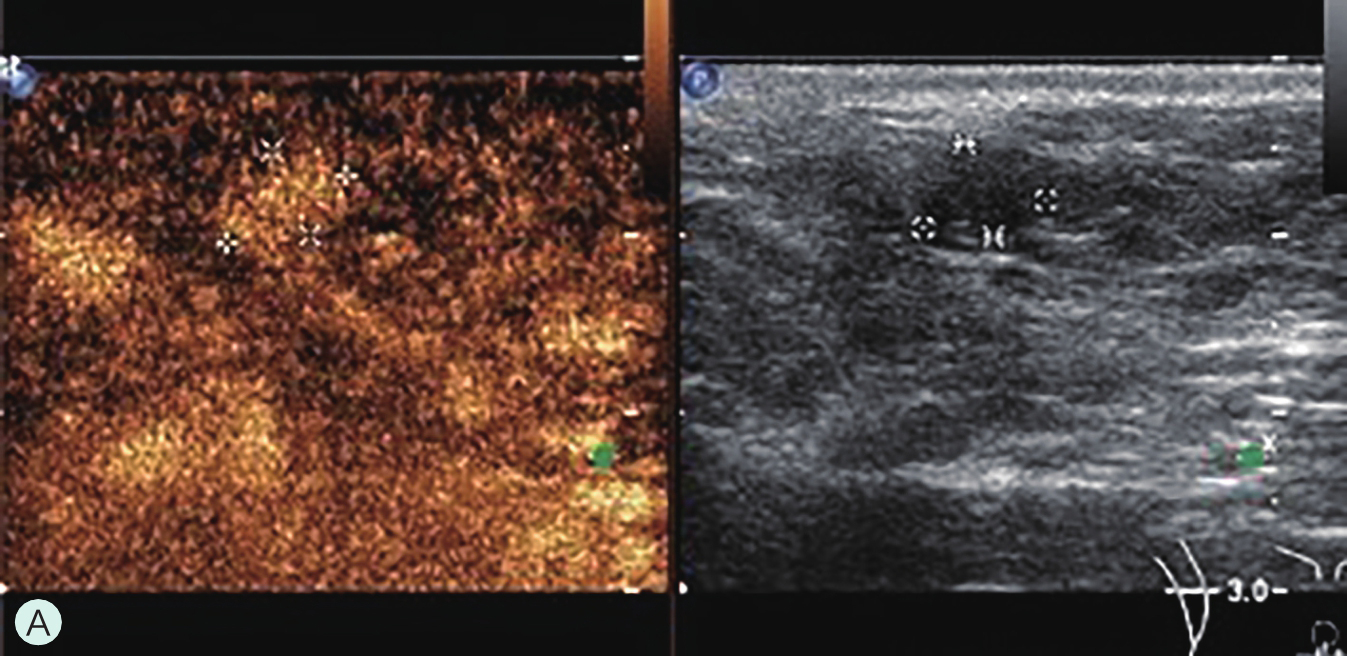

造影前应用传统灰阶超声全面扫查患侧乳腺及腋窝,重点扫查既往检查可疑病灶所在象限,结合既往检查确定超声造影靶目标及造影切面。评估病灶所在部位乳腺腺体致密性,二维及彩色多普勒(CDFI)超声常规检测肿块的大小、形态、边界、内部回声、血流及与周边组织的关系,充分利用现有超声新技术(如弹性成像)全面评估病灶。当病灶位置表浅、位于乳头后方或与探头耦合不佳时,可应用超声垫。

图2-2-1 确定造影病灶

A.病灶二维图像;B、C.病灶CDFI图像;D.同侧腋窝淋巴结情况;E.病灶弹性成像图像

A.同步测量病灶大小与高增强范围;B.勾勒病灶与增强范围;C.定量分析